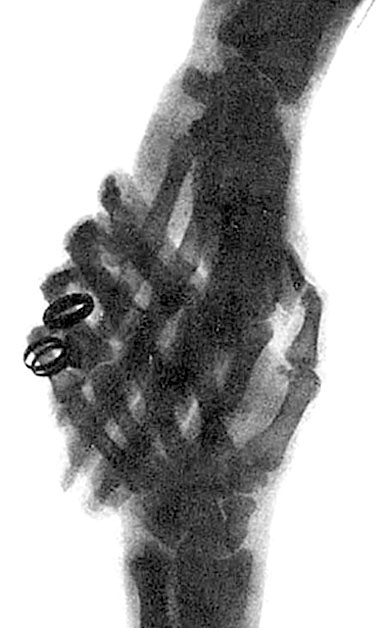

Иллюстрация к книге — Солнечное вещество и другие повести, а также Жизнь и судьба Матвея Бронштейна и Лидии Чуковской (сборник) [i_035.jpg]

Рука, сфотографированная лучами Рентгена

Это тоже один из первых снимков, сделанных Рентгеном. Рука на фотографии – жены Рентгена. Видно кольцо, надетое на палец.